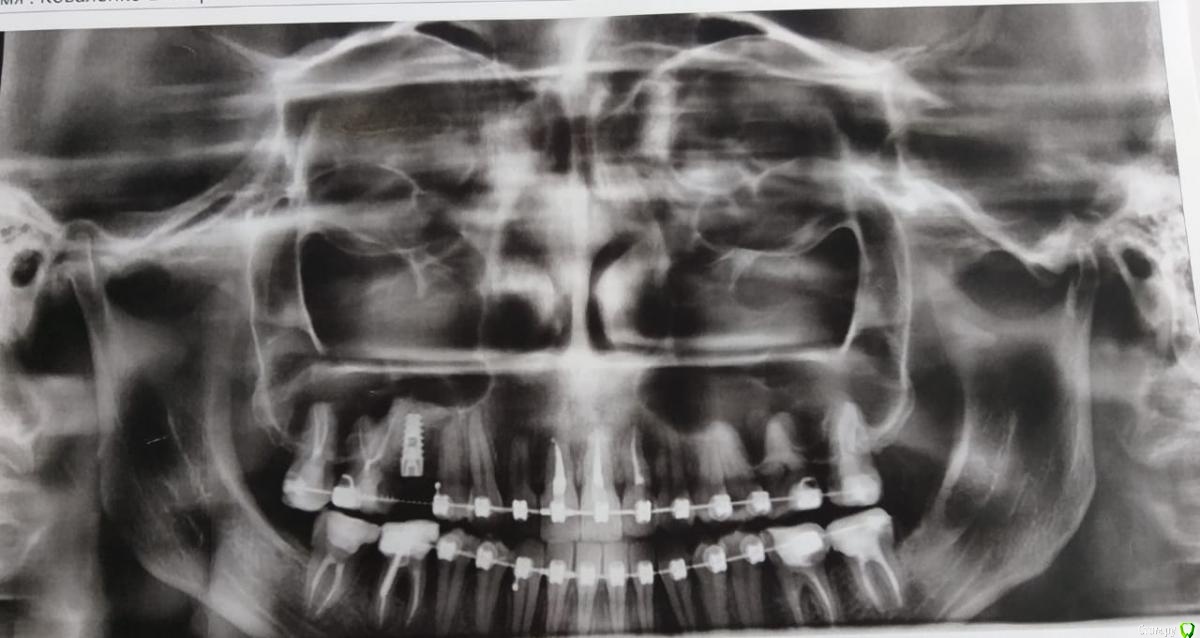

Ирина Артемьева Опубликовано 19 октября, 2020 Поделиться Опубликовано 19 октября, 2020 Всем здравствуйте! В апреле этого года у меня была проведена операция синус-лифтинга с одновременной имплантацией вверху справа. После операции вроде бы было все более менее нормально, но через месяц после операции у меня начался гайморит (гайморит у меня хронический, врач об этом знал). Лор назначил мне лечение - антибиотик кларитромицин 7 дней, отривин, ирс-19. После лечения насморк заложенность и температура прошли, НО начались боли в области имплантата, с правой стороны постоянно что -то давит в щеке, болит голова,больно двигать челюстью с правой стороны. Я пошла к стоматологу, мы сделали КТ - на нем все ок. Через месяц ко всем вышеуказанным симптомам добавилось то, что у меня начало закладывать правое ухо. Я пришла к лору - лор ничего не увидел и отправил меня назад к стоматологу. Стоматолог сделал опять КТ и на нем все нормально!! Решили подождать еще месяц и далее ко всему тому что было у меня еще начал болеть правый глаз, хотя с глазами проблем не было никогда!!! На сегодняшний день что я имею - у меня постоянно давит что-то в районе правой щеки, болит челюсть справа, болит голова шея, закладывает ухо и болит глаз. Я предлагала стоматологу удалить имплантат, потому что устала мучаться, плачу каждый день((( Но мой стоматолог категорически против, т.к. не видит по КТ никаких проблем. Куда мне еще обратиться? Что это может быть вообще? Уже все равно на потраченные деньги, хочется вернуть свое здоровье. Прикрепляю последнее КТ от 1 сентября 2020 года Ссылка на комментарий

red_butler Опубликовано 19 октября, 2020 Поделиться Опубликовано 19 октября, 2020 Это не Кт Ссылка на комментарий

Ирина Артемьева Опубликовано 19 октября, 2020 Автор Поделиться Опубликовано 19 октября, 2020 Это не КтЭто стоматолог распечатал фото как я поняла с КТ Ссылка на комментарий

red_butler Опубликовано 19 октября, 2020 Поделиться Опубликовано 19 октября, 2020 Это стоматолог распечатал фото как я поняла с КТЭто обычный панорамный снимок, нужна томограмма с придаточными пазухами носа Ссылка на комментарий